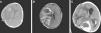

En el día +9, coincidiendo con neutropenia grave, inicia proceso febril de 4 días de evolución, evidenciándose condensación neumónica y aislamiento en los hemocultivos de Streptococcus pneumoniae y Staphilococcus aureus. Tratamiento con antibioterapia parenteral de larga duración. En el día +14 se apreció un 13% de blastos en médula ósea, determinando el cambio hacia paciente de alto riesgo. En el día +22, tras la administración de la quinta dosis de L-asparraginasa, inicia cefalea intensa y un día después se objetivan somnolencia y hemiplejía braquiocrural izquierda que motivan la realización de TAC y RMN cerebral, encontrándose trombosis venosa del seno longitudinal superior, transverso y sigmoideo derecho que llega hasta la vena yugular interna y el catéter central, y hemorragia intracraneal parietal derecha, además de ocupación de senos maxilares y mastoiditis derecha (fig. 1). La paciente fue trasladada a la Unidad de Cuidados Intensivos. Se instauró tratamiento con heparina sódica intravenosa, presentando a las 48h nuevo sangrado parenquimatoso con signos de herniación, por lo que se realizó craniectomía descompresiva, a pesar de lo cual posteriormente presentó resangrado y persistencia de la trombosis masiva (fig. 2). Se suspendió la administración de asparraginasa manteniendo el resto de quimioterapia, presentando en el día +30 una enfermedad mínima residual del 2,3%. Después del diagnóstico de trombosis se evidenció disminución de las tasas de antitrombina iii (33%) y de fibrinógeno (<0,5g/l), y el estudio de trombofilia mostró mutación de la protrombina G20210A en heterocigosis y anticoagulante lúpico positivo. Ante la progresión de la leucemia y la intensa afectación neurológica se decidió evolutivamente realizar tratamiento paliativo, falleciendo la paciente a los 2 meses del ingreso. En el estudio familiar la madre presentó mutación de la protrombina.

Imágenes de TC (A) y resonancia magnética (B y C) evolutivas. Progresión del hematoma parietal hacia lóbulo frontal que precisa craniectomía descompresiva (A y B). C) Estadio final con aumento del edema y por tanto de su efecto compresivo sobre el parénquima cerebral que protruye sobre la craniectomía. Hematomas intraparenquimatosos de nueva aparición en hemisferio cerebral derecho. Hematoma subdural y hemorragia intraventricular de nueva aparición. Hidrocefalia tetraventricular.